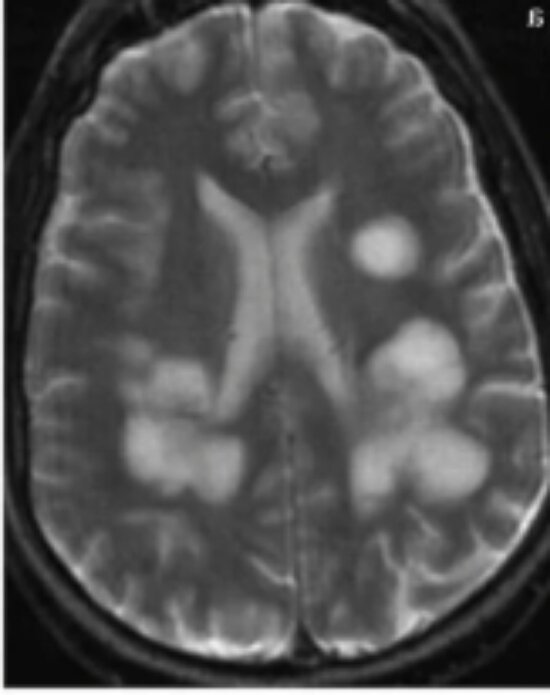

Мрт не моё. Моё на диске. Примерно так сейчас выглядят облака в моей голове.

Первым пунктом в моём списке было МРТ головного мозга. Два года МРТ делали с контрастом. В марте 20 года контраст ничего не показал, за то без него всё стало видно. Мне сказали, что есть очаги поражения головного мозга, которые похожи на облака. Не удивлена в 18 году и в 19. Их там было два. Ну, ладно очагов мало. Из-за этого у меня проблемы со слухом, начинаются проблемы со зрением и координацией.

В этот раз очаги увеличились в размерах. То-то я чувствую что-то мне не хорошо. Грусть, тоска я в домике.